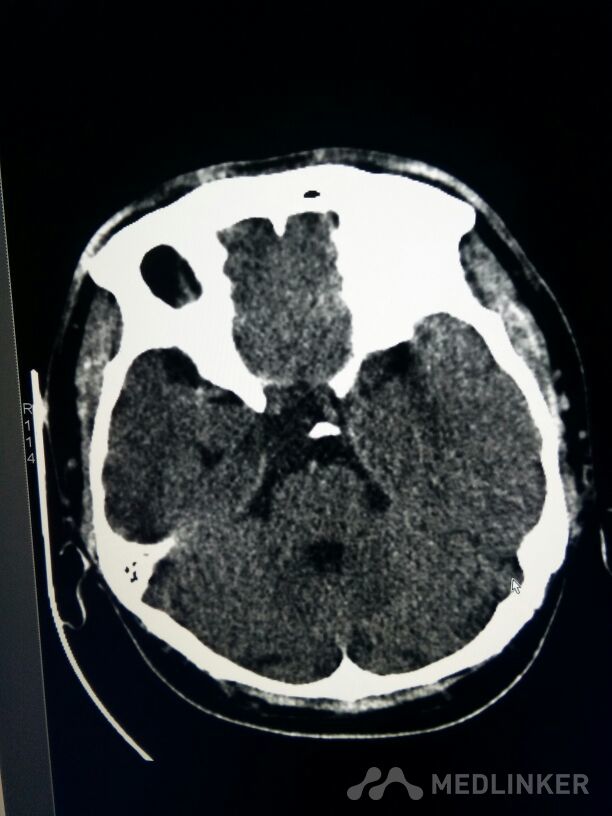

考虑表皮样囊肿?

表皮样囊肿